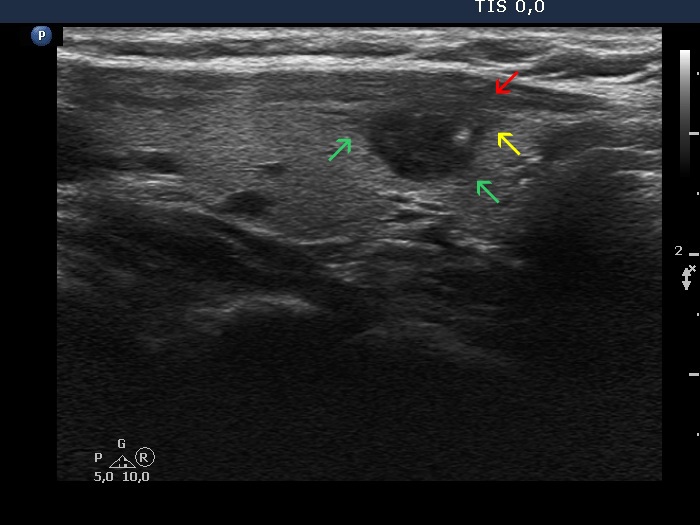

Benign nodule (cytology) - case 2127

Transverse scan

Longitudinal scan

In this case the thyroid has a large nodule presenting isoechoic areas and the extranodular parenchyma is also isoechoic (yellow arrows). Therefore, a clear distinction is possible in only those parts where halo can be identified in the form of hypoechogenic or hyperechogenic lines between the nodular and non-nodular tissue (red arrows).